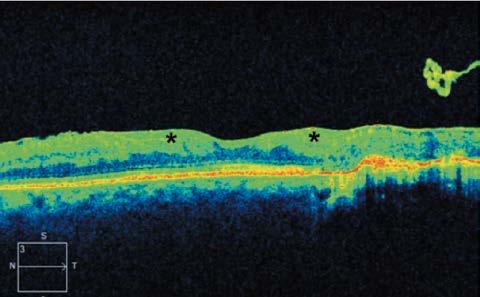

Los cambios patológicos más específicos, como la desorganización de las capas internas de la retina (DRIL; Figura 1), solo pueden apreciarse mediante OCT y se han identificado como marcadores del potencial visual y predictores de la progresión de la RD.4 Del mismo modo, la alteración de la retina externa (Figura 2) y el daño temprano de los fotorreceptores pueden indicar una enfermedad más avanzada con un pronóstico visual desfavorable.5

Figura 1. Tomografía de coherencia óptica de un varón de 41 años con antecedentes de retinopatía diabética proliferativa que muestra una desorganización de las capas internas de la retina (asteriscos).